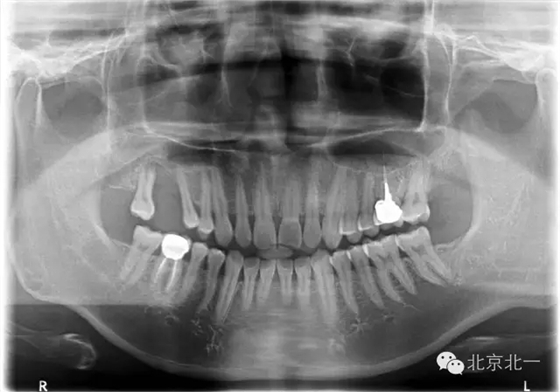

圖二:手術前全景片